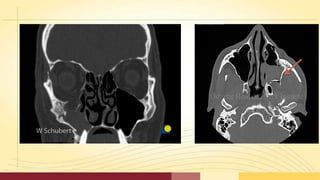

• Plain films and Computed Tomography have their place in

determining the type,location, magnitude, and direction of

displacement of zygomatic fractures.

• This includes,

Water 's view, Submentovertex view, Computed Tomography.

• CT scans allow complete assessment orbital

floor and walls.

• The axial scan is helpful in evaluating the medial and

lateral walls, and the coronal scan defines the extent of

injury to the orbital floor